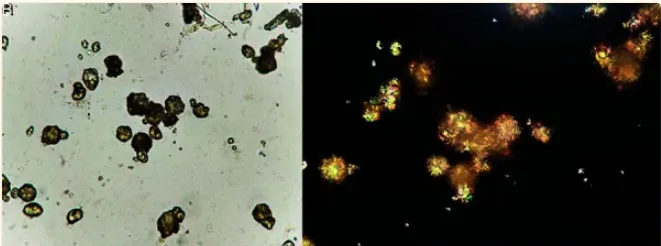

Devido à persistência da cristalúria de ácido úrico, foi solicitada uma revisão manual do sedimento urinário por um observador experiente, que identificou a seguinte imagem:

Na análise urinária os cristais apresentavam formato esférico irregular e estrias radiais, coloração amarela a marrom e forte birrefringência positiva. Com suspeita clínica de IRA associada a cristais de SMX, foi realizada a alcalinização da urina com bicarbonato de sódio. O paciente respondeu favoravelmente, com resolução completa da IRA.